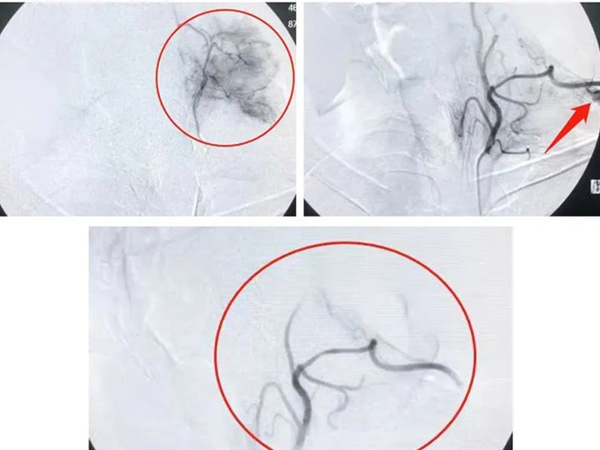

其中还有一名是春节前那例急诊大出血的患者,不仅止血效果立竿见影,肿瘤也小了特别多,近日又进行针对肿瘤的介入治疗。患者在第一次止血救治成功后,坚定的相信我院能给他带来更好的疗效,而且,肿瘤也缩小了,更坚定了生存的信心。术后,他和家属说,张主任往我哪个位置肿瘤给药我都感觉得到,真的太神奇了。

年前止血手术

年后肿瘤介入手术